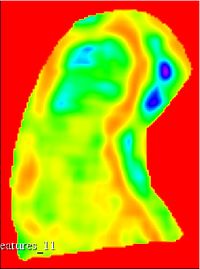

Texture feature maps

Co-occurrence texture feature maps